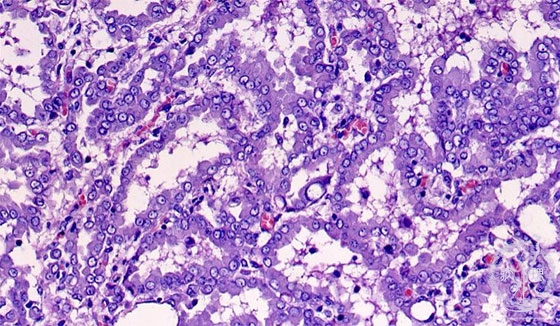

胸膜中皮腫ミクロ像(HE強拡大)

ミクロ像(HE強拡大):腫瘍細胞は腺管様構造、偽乳頭状構造を示しながら浸潤性増殖している。 HE染色のみでは肺腺癌との鑑別が困難なことがある。